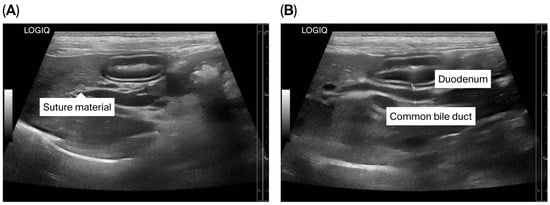

The puppy’s anesthetic recovery went well. Intravenous fluid therapy using 0.9% NaCl (General Hospital Products Public Co., Ltd., Pathum Thani, Thailand) and antibiotic therapy using cefazolin intravenously (20 mg/kg q12h) were continued for postoperative care. Tramadol (2.5 mg/kg q12h, IV; Tramada-100®, L.B.S. Laboratory Ltd., Part., Bangkok, Thailand) was administered for analgesia. Upon recovery, the puppy was bright with a good appetite. The puppy was discharged 72 h after surgery with an uneventful postoperative recovery, and the sutures were removed seven days later. At three months post-operation, ultrasonography demonstrated a smaller size of the CBD (diameter 0.35 cm) (Figure 7A,B). The dog remained clinically healthy without any relevant complications for 19 months post-operation. Unfortunately, the dog died at the age of 1 year 10 months due to aspiration pneumonia of unknown cause.

Figure 7. Ultrasonographic findings of the biliary system after surgery. (A) Suture material near the common bile duct (CBD) is shown; (B) The CBD is mildly dilated.